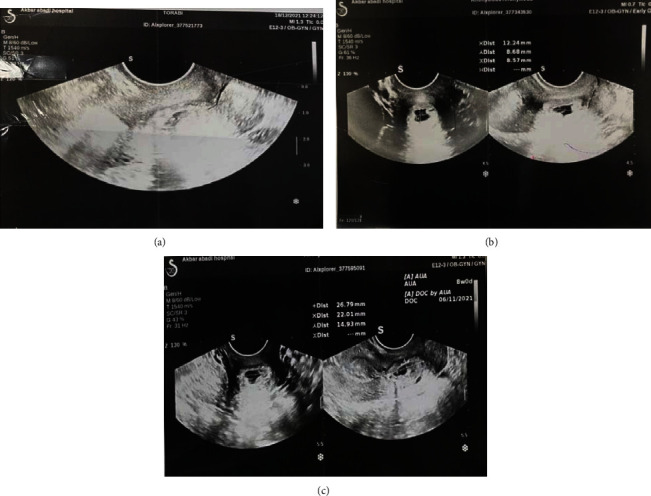

In the transvaginal ultrasonography, the pregnancy sac and the yolk sac with the embryonic pole with a positive fetal heart rate (FHR) were presented and located near the internal os, at the beginning of the cervical canal. The crown-rump length (CRL) was 4 mm, and the patient had normal endometrial thickness. Most of the pregnancy sac was seen in the proximal cervix, and there was a small part in the lower segment. The pregnancy bag had more blood than the other areas. There was a mild decidual reaction around the amniotic sac. Therefore, a cervical pregnancy was diagnosed, and the patient was hospitalized for further treatment (Figure 1).

Figure 1.

The obstetric ultrasonography shows the pregnancy sac and the yolk sac with the embryonic pole located near the internal os.

Serial ultrasonography was done, and there was a fetal echo (with FHR +) in the pregnancy bag on days 7 and 14 (Figures 2 and 3), so one cc KCL was injected into the pregnancy bag under the guidance of ultrasound.

Figure 2.

The 2nd ultrasonography, a fetal echo (with FHR +) in the pregnancy bag.

Figure 3.

The 3rd ultrasonography, a fetal echo (with FHR +) in the pregnancy bag.

Serial ultrasonography was done. As in the 3rd ultrasonography, there was a fetal echo (with FHR +) in the pregnancy bag (Figure 3).